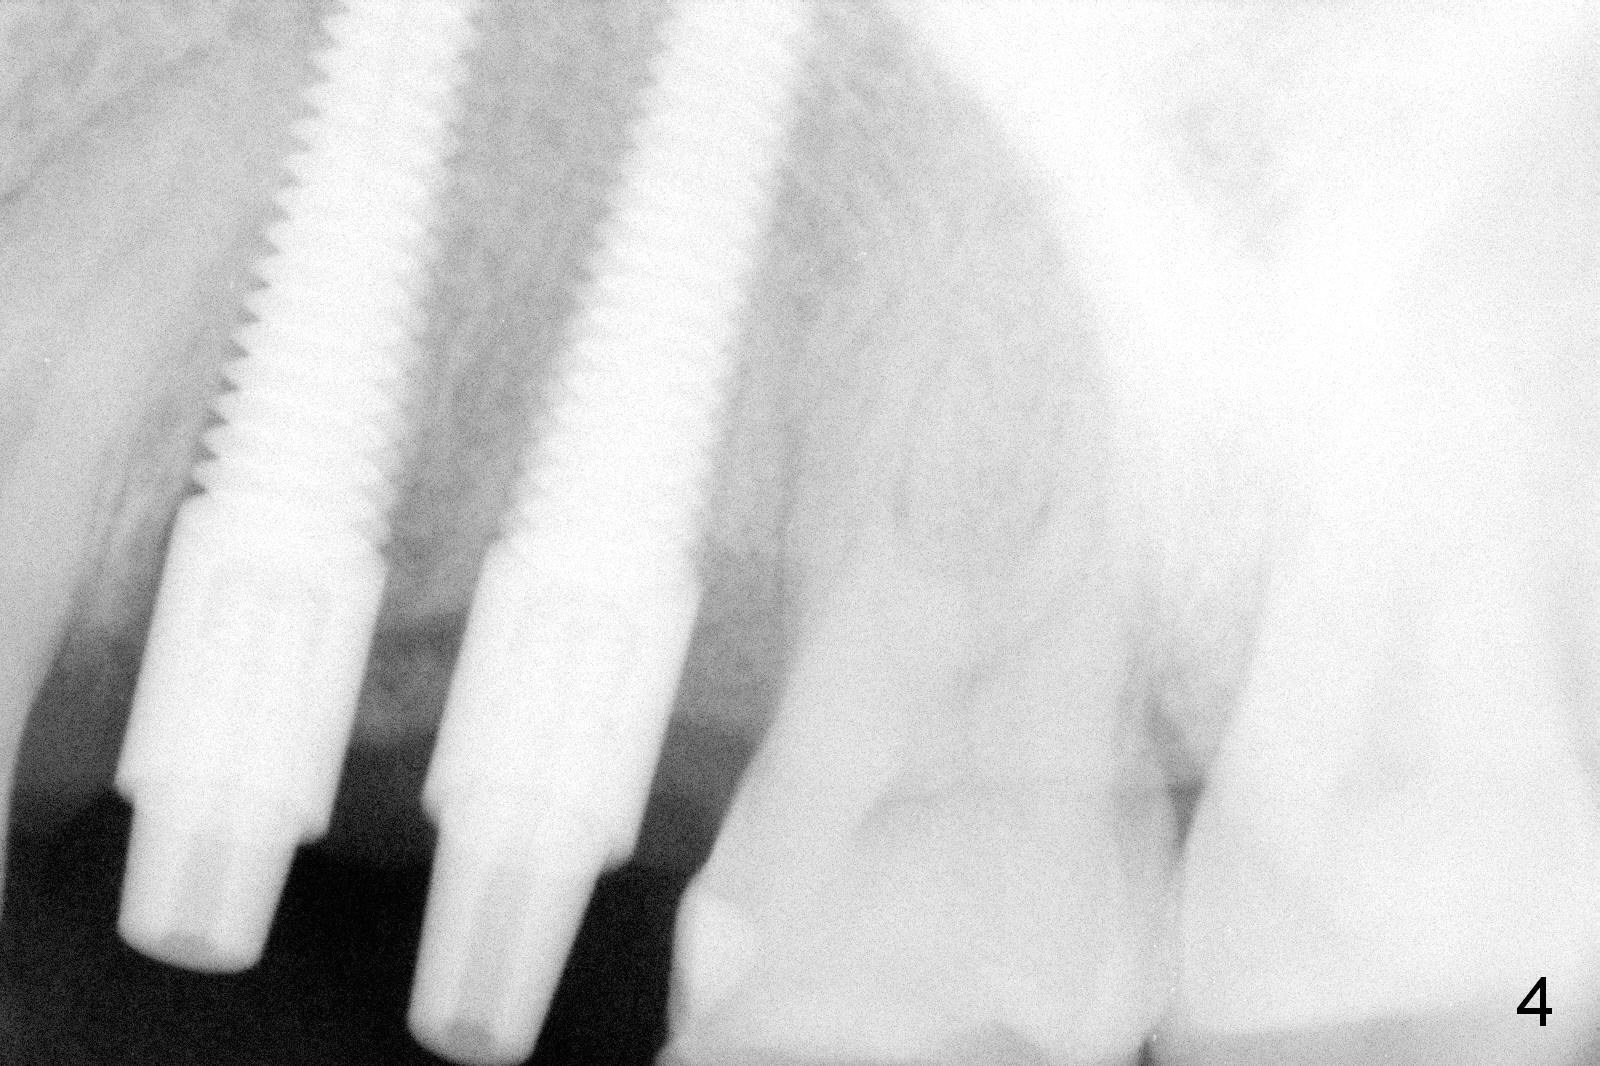

Taking 2 additional PAs with sensor 1 is frustrating (Fig.1,2), no apices shown.  Osteotomy is done smoothly with 2 mm pilot drill at 20 mm, 2.5 mm reamer at 17 mm, and 3 mm reamer at 14 mm and 4.5x20 mm tap at 17 mm.  The 1st intraop PA is taken with sensor 1 when 2 of 4.5x20 mm implants are placed (Fig.3); the implant at #12 is close to the root of the tooth #11.  The 2nd PA is taken with sensor 2: the apex of #11 touches the implant at #12 (Fig.4).  There is no separation when panoramic X-ray is taken (Fig.5).  Effort is exerted to re-direct the osteotomy twice (Fig.6: tap; Fig.7: implant) without success.  When the implant is removed, a PA is taken; it appears that the root of the tooth #11 has no damage (Fig.8).  To obtain the best recovery, socket preservation is carried out with 50/50 cortical/cancellous allograft mixed with Osteogen (Fig.12 *) and Collagen Dressing (Fig.9: #12).  A 2 (or 3)-unit provisional bridge (Fig.10: #12,13) is fabricated over the implant (Fig.9 I)/abutment (A) to cover these 2 sockets.  After acid etching #11 D surface (Fig.9 >) and relining (Fig.11 *), the provisional bridge is bonded to the tooth #11 (Fig.11,12 black >) so that bone graft will be less likely dislodged.